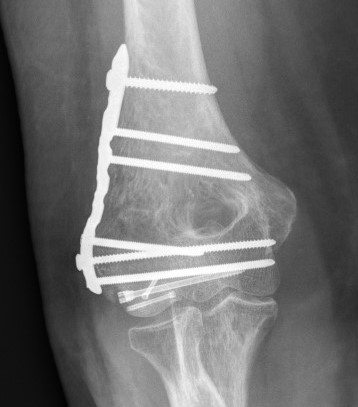

Fixation

Headless compression screws AP / PA

Posterolateral plate

Lateral approach and ORIF

- +/- postero-lateral plate

ORIF with PA screws and posterolateral plate

Large capitellum fracture / lateral column ORIF with plate and screws